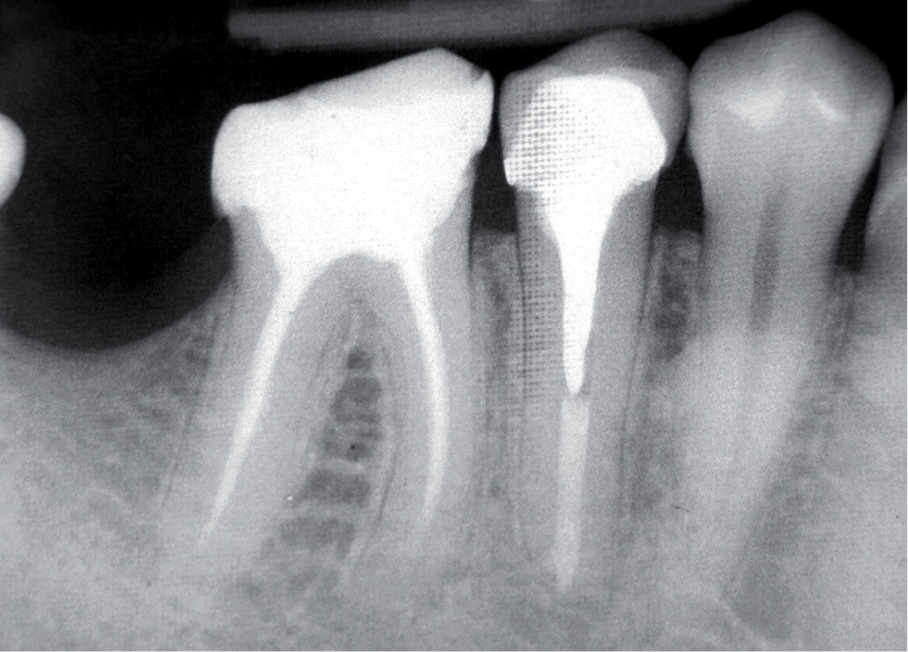

W zębach z zakończonym rozwojem korzenia możemy mieć do czynienia z szerokimi wierzchołkami na skutek przywierzchołkowej resorpcji korzenia na tle zapalnym (ryc. 1a-d, s. 6-7), w przypadku zębów po resekcji wierzchołka korzenia (ryc. 2a-d, s. 7), jak również w przypadku zębów, w których doszło do jatrogennego poszerzenia wierzchołka na skutek leczenia kanałowego (ryc. 3a-c, s. 8).